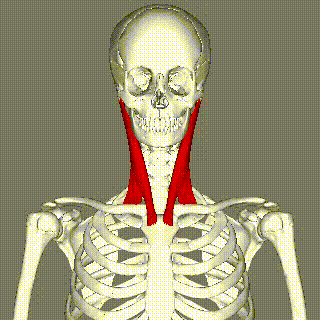

最终,CT在该女性的胸锁乳突肌上,扫描到一根5.1厘米长的异物。

图片来源于The Journal of Emergency Medicine胸锁乳突肌是颈部众多肌肉中最大最粗的一条,离食道、气管远远的。鱼刺是怎么过去的呢?